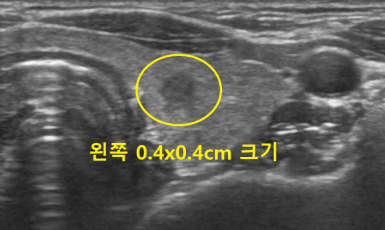

282번째 유방암 진단사례 (2020년2월6일) 3일전에 우연히 만져본 가슴에서 왼쪽 유방에 단단한 혹을 발견한후 진료위해 내원한 환자분이셨습니다. 진찰상..

작성자 레이디유 작성일 02-12 조회 10